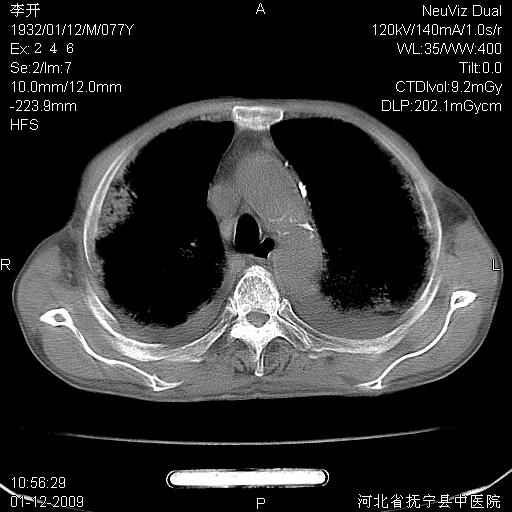

以下是引用黑白光影在2009-1-19 16:49:00的发言:[br]心衰肺水肿;心包、胸腔积液;冠脉钙化;肺部感染。